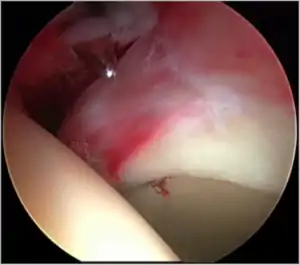

Standard arthroscopic treatment of symptomatic cam FAI involves debridement (resection) or repair of any labral [10] and chondral injuries [11] in the central compartment of the hip, and subsequent reshaping of the head-neck junction of the upper femur (osteochondroplasty) in the peripheral compartment [12][13] using high-speed motorised burrs that are similar in design to a dentist's drill (see fig. 9).